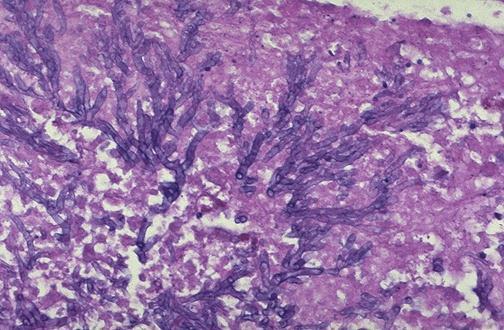

Q: A 78 year old man is found to have a 4.2 cm left upper lobe mass with central cavitation.

Histology of the mass is shown above. What is the expected staining pattern of this mass?

1.TTF1+, napsin A+, p40-

2.TTF1+, napsin A-, p40+

3.TTF1-, napsin A-, p40+

4.TTF1-, napsin A+, p40+

Answer C

TTF1-, napsin A-, p40+.

• The radiographic description and cytology specimen is consistent with squamous cell carcinoma, which typically stains positive for p40.

• Answers A, B and D are incorrect because TTF1 and napsin A are typically positive in adenocarcinomas.

• Of note, TTF1 can also positive in tumors of neuroendocrine lineage and may also stain background benign bronchial cells.